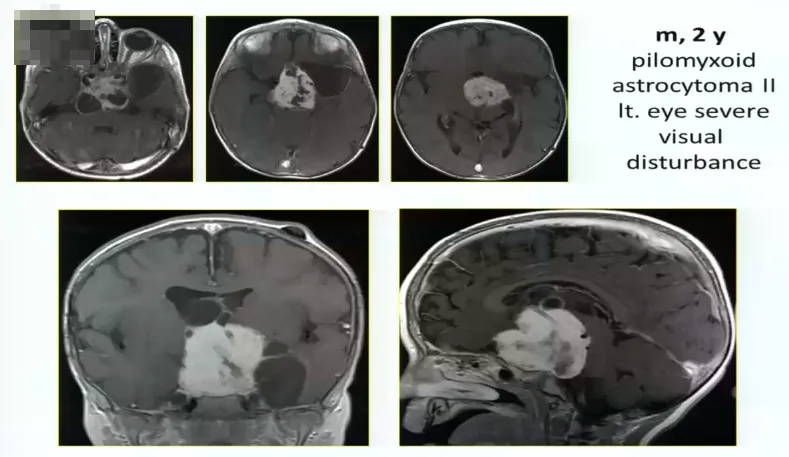

手术病例2:

2岁男孩,毛状黏液样星形细胞瘤2级,严重的左侧视觉障碍,肿瘤巨大

术中情况:采取眶颧入路,肿瘤非常大,累及向上向下,需要宽广的视野。

术后情况:肿瘤全切,术后一年,孩子状态良好。小儿肿瘤放化疗专家为其进行后续治疗。